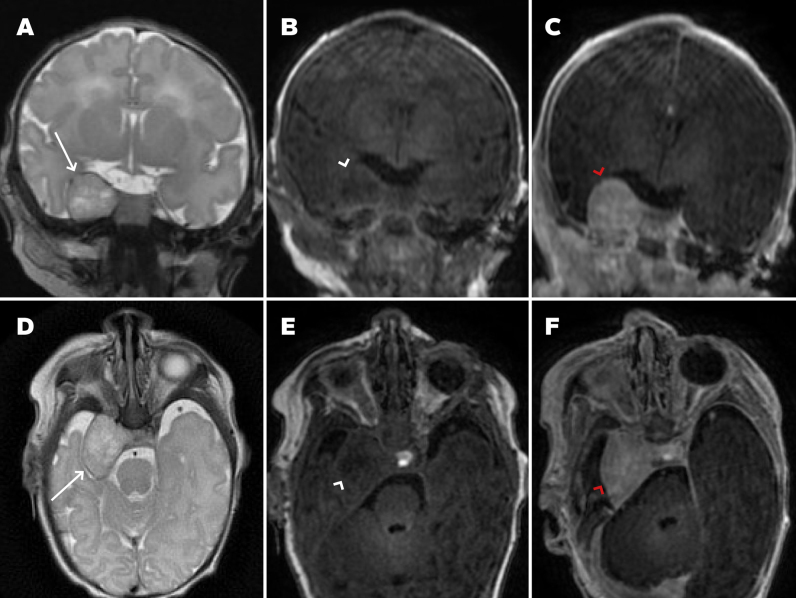

Observations: A 28-year-old female underwent routine fetal ultrasound at 32 weeks' gestation, revealing a 1.8-cm perithalamic lesion. Fetal MRI at 33 weeks confirmed an extra-axial mass in the right middle fossa with a dural attachment. Postnatal MRI on day 1 of life demonstrated imaging features consistent with an IH. Given the neonate's asymptomatic status, conservative management was pursued. Serial MRI at 10 weeks and 6 months showed progressive lesion regression, with near-complete resolution. The infant remained asymptomatic with normal neurodevelopmental progress.